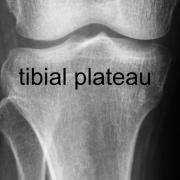

In this X-ray of the tibial plateau you can see the two tibial spines in the centre of the tibial plateau - they are where the cruciate ligaments attach, but you cannot see that here because the ligaments do not show up on X-ray.

The tibial spine is a raised area of bone in the middle of the tibial plateau, and related to the attachment of the cruciate ligaments.